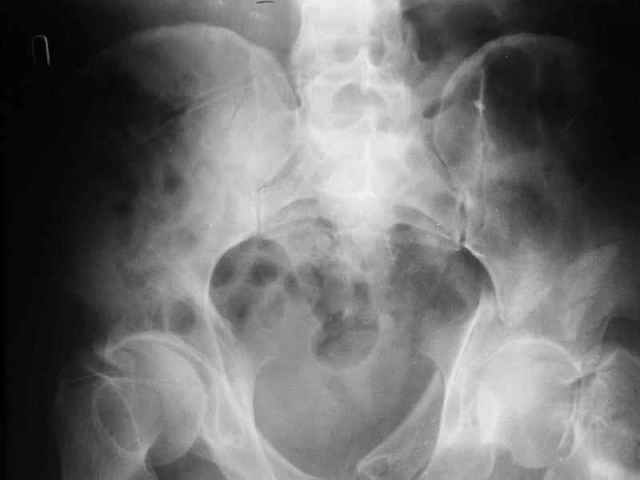

Больной 18 мая 2003 года в автоаварии получил перелом левой вертлужной впадины, вывих бедра. Госпитализирован в один из стационаров области.Вывих вправлен. В последствии бедро вывихивалось еще дважды. На консультацию был представлен снимок от 19.05.03г., больной переведен к нам 3.06.03г. Снимок при поступлении - перелом впадины, задне-верхний вывих бедра. 05.06.2003 г. выполнено открытое вправление вывиха левого бедра и остеосинтез стенки вертлужной впадины двумя винтами. Послеоперационный период без осложнений. Объем движений в левом тазобедренном суставе восстановился полностью. Выписан на амбулаторное лечение в удовлетворительном состоянии с рекомендациями 3 месяца ходить на костылях без нагрузки на оперированную конечность. На контрольных рентгенограммах левого тазобедренного сустава 13.10.2003 г. - признаки консолидации перелома; плотность, форма головки и состояние суставных поверхностей удовлетворительные. Разрешена дозированная осевая нагрузка, на конечность с использованием дополнительной опоры. 19.12.2003 г. больной обратился с жалобами на боли в левом тазобедренном суставе. На рентгенограммах левого тазобедренного сустава 19.12.2003 г., 20.02.04г. - асептичекий некроз головки бедра. 5.04.04г. - эндопротез. Сейчас ходит без трости, не хромает. Особенность эндопротезирования - при удалении винтов прослежена линия перелома заднего края впадины и предложено установить чашку несколько меньшего диаметра, чтобы она была покрыта несломанной частью.